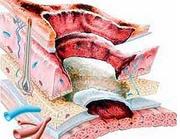

无机碱皮肤损伤

酸碱灼伤

亚急性硬膜外血肿

外伤性硬膜下积液

急性硬脑膜下血肿

慢性硬脑膜下血肿